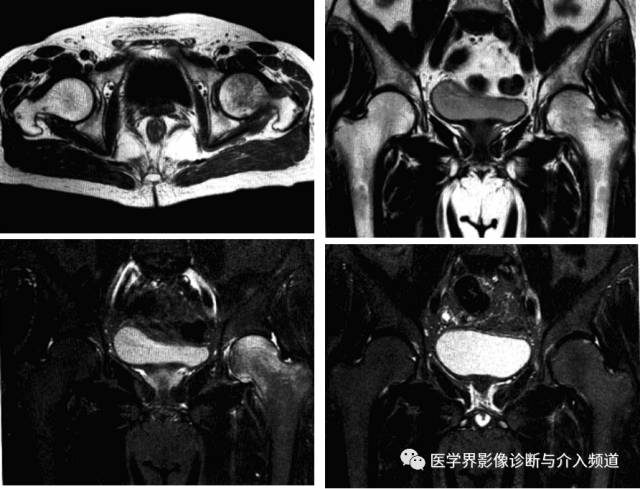

强直性脊柱炎累及髋关节

系累及中轴骨及近端大关节的血清阴性脊柱关节病。病变对称侵及骶髂关节、椎间小关节、附件韧带和近躯干的大关节,最后导致纤维性或骨性强直和畸形。髋关节是本病最常累及的关节,约占50%。

影像诊断:X线片为主要检查手段,MRI能显示早期髋关节改变。

1、平片:双侧对称受累,早期骨质疏松,关节囊膨隆,股骨头及髋臼骨质侵蚀糜烂;中期关节间隙一致性狭窄,软骨下囊性变,关节面边缘骨质增生,坐骨结节、坐骨耻骨支及股骨大转子可伴骨膜炎;晚期股骨头内移、髋臼内突,关节腔闭锁呈骨性强直。

2、CT:早期少量关节腔积液,可伴髂腰肌囊扩张,同时股骨头骨质疏松,股骨头及髋臼缘囊状、虫蚀状骨质缺损;中期关节面边缘硬化、囊变、骨赘形成,股骨头基底滑膜附着处增生,髋关节间隙均匀一致性狭窄消失,双侧髋对称性骨性强直,股骨头及髋臼可普遍性肥大。

3、MRI:①关节积液,关节间隙增宽,②滑膜增厚,增强后明显强化,③关节软骨水肿,④关节面软骨信号改变,炎性血管翳增生,信号强度不均,⑤软骨下囊性变,⑥关节骨性强直。